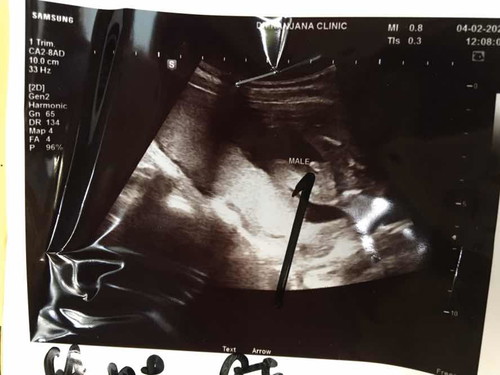

แบบนี้ผู้ชายใช่ไหมค่ะ ?

ใช่คะแม่ ผช คะ